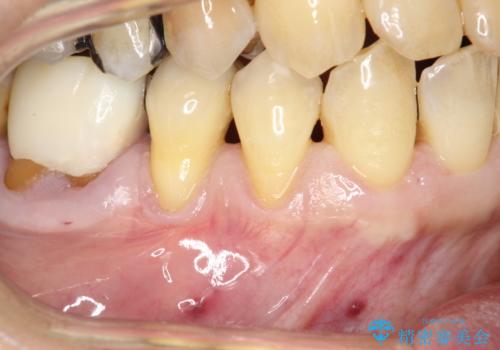

徐々に下がってきた歯肉へ再生療法(歯冠側移動術と結合組織移植術の併用)を施術し、丈夫な歯肉を獲得させた症例

担当医 林佳士登